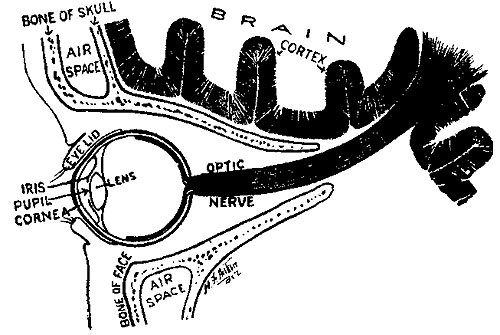

260 The Apparatus of Vision

263 A School Eye-Test